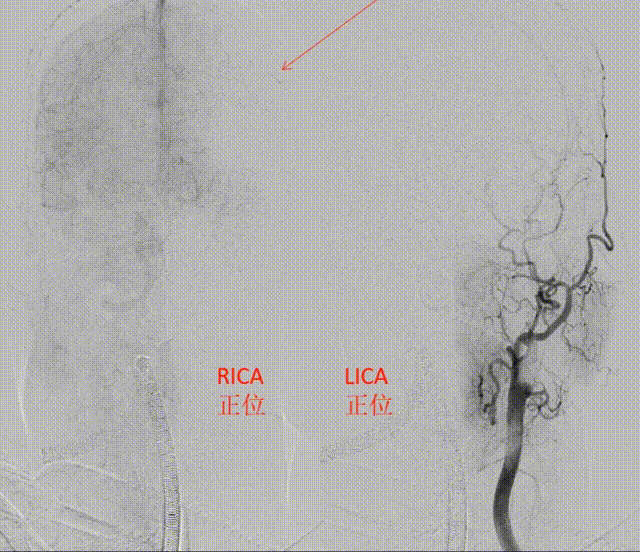

第三个选择:颈外动脉取栓否?直接贴敷支架?

栓塞机制、出血风险高,避免支架植入。

经长鞘释放保护伞后,在颈总造影

微导管颈外到位造影

ET2释放后造影

颈外拉栓后造影

保护伞取栓、长鞘带接抽吸泵负压

左侧颈总动脉造影

第一次颈内末端支架拉栓

保护伞“SWIM”取出的血栓